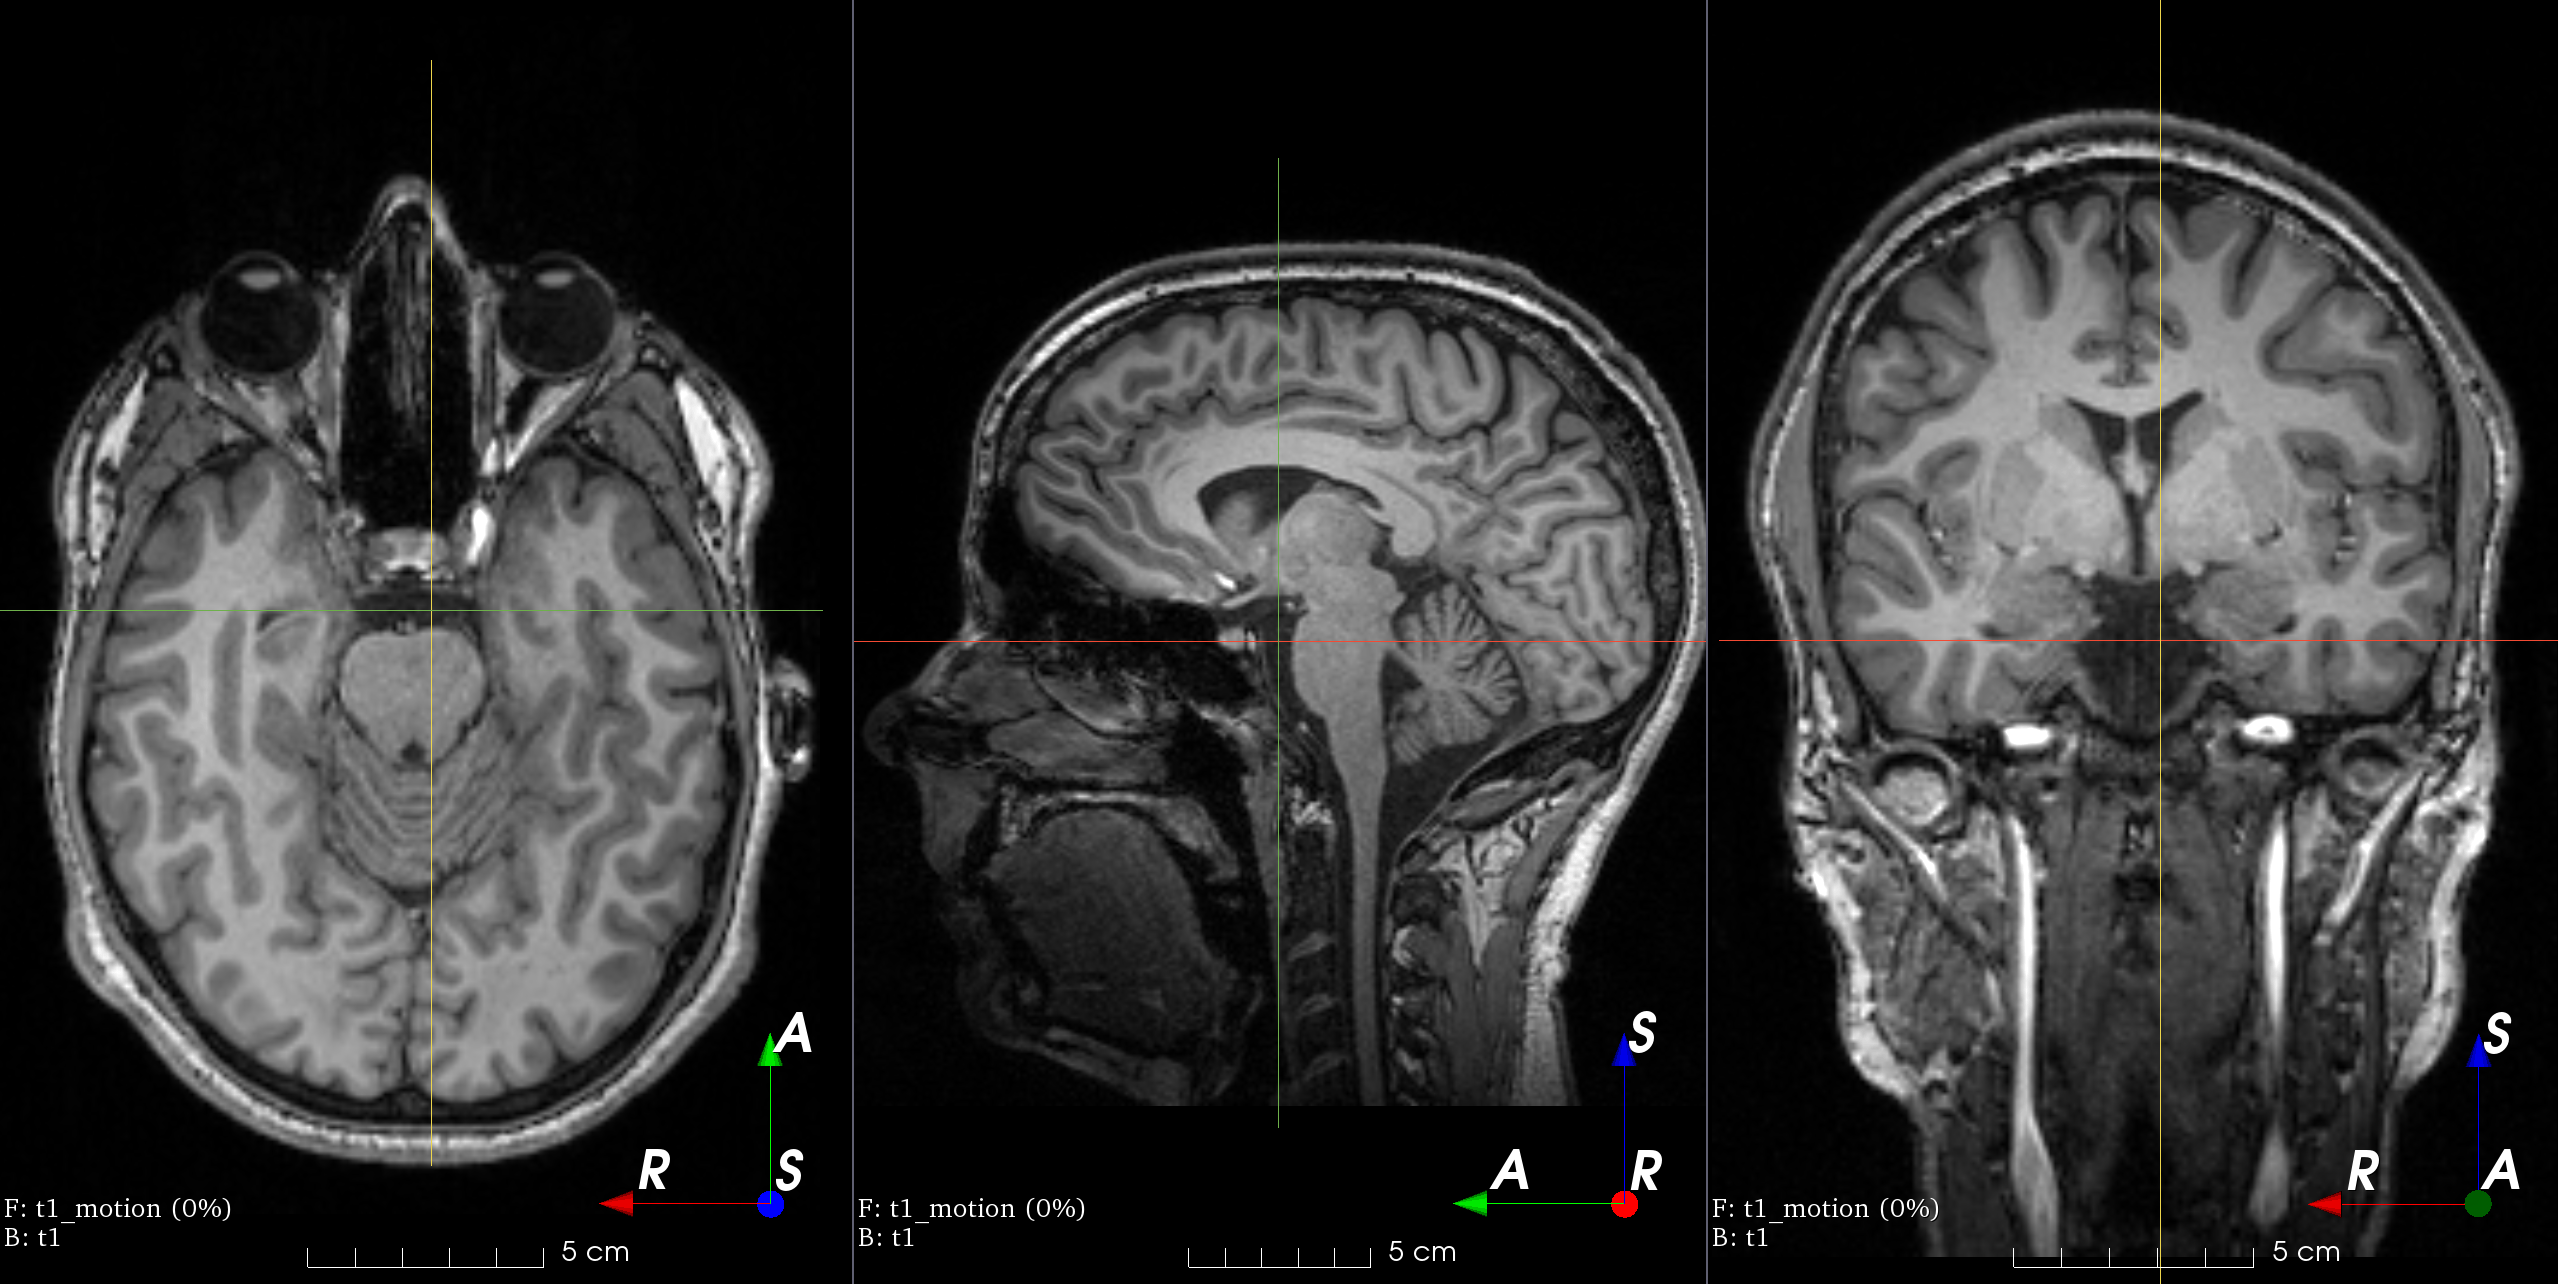

Add random MRI motion artifact.

Magnetic resonance images suffer from motion artifacts when the subject moves during image acquisition. This transform follows Shaw et al., 2019 to simulate motion artifacts for data augmentation.